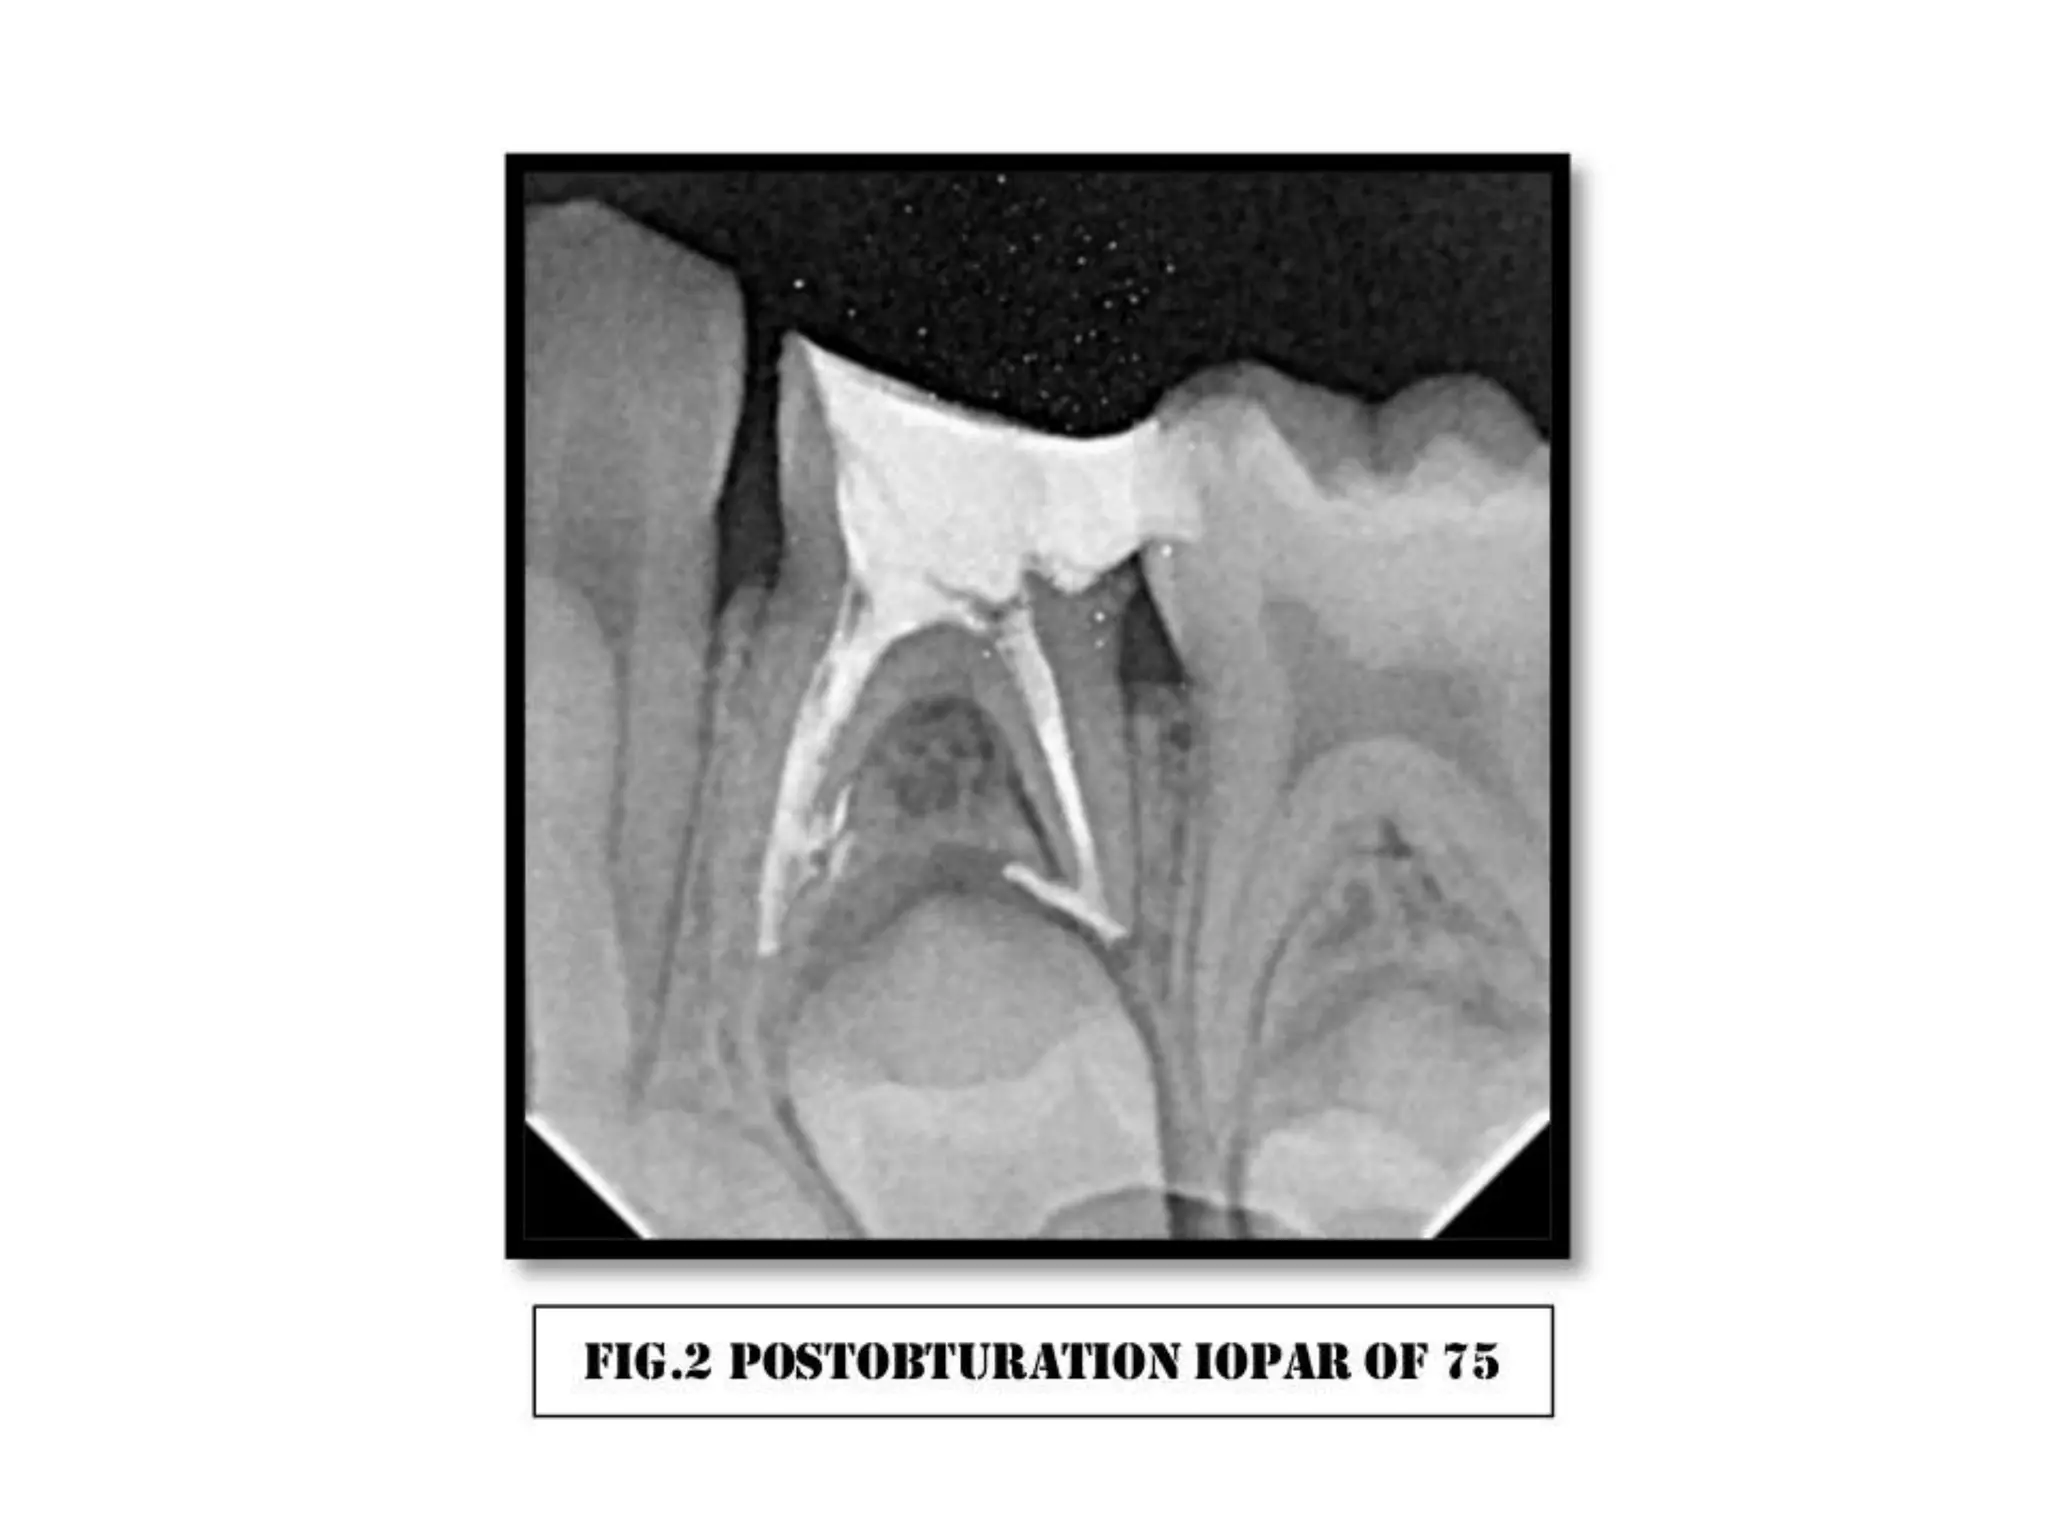

Gallbladder Stones Treatment__ in Hyderabad, India. Pulpectomy with ss crown case 3